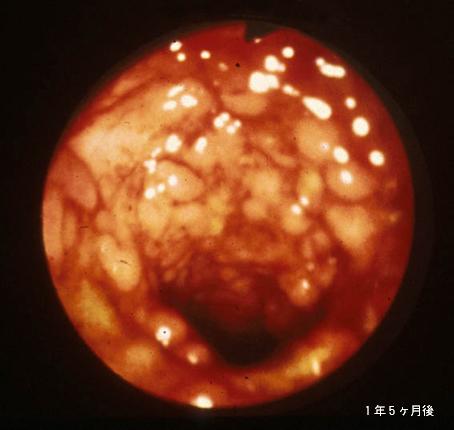

疾患(病理主体)の分類炎症性・潰瘍性疾患/潰瘍性大腸炎

部位(臓器別)大腸/上行

検査方法内視鏡